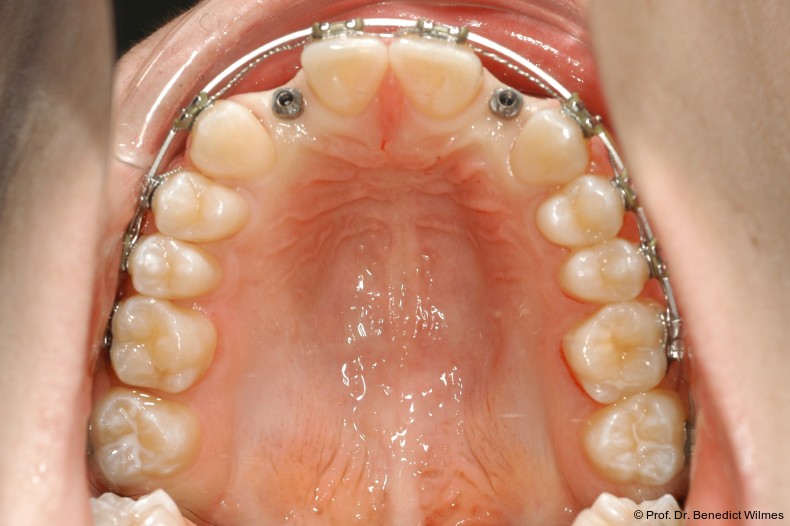

Ein 14-jähriger Patient wurde bei Aplasie der beiden oberen seitlichen Schneidezähne mit dem Ziel der beidseitigen Lückenöffnung kieferorthopädisch therapiert (Abb. 1a+b). Zum Ende der kieferorthopädischen Behandlung wurden zwei Miniimplantate in Regio 2er als temporärer Zahnersatz inseriert (Benefit System, PSM, 2 x 13 mm, Abb. 2a+b). Nach Abdrucknahme wurden Kronen auf den Peek-Abutments modelliert und diese mit Kunststoff auf die Abutments geklebt (Abb. 3a–d). In den Abbildungen 3 und 4 sind die klinischen und röntgenologischen Nachkontrollen innerhalb der nächsten achteinhalb Jahre dokumentiert. Man erkennt einen sowohl in der Höhe als auch in bukkopalatinalen Breite verbleibenden gesunden Knochen ohne Anzeichen einer Atrophie. Im Alter von 23 Jahren wurden die definitiven Implantate ohne die Notwendigkeit einer Augmentation eingesetzt (Abb. 5) und nach Einheilung prothetisch versorgt (Abb. 6a–e und Abb. 7a–c).